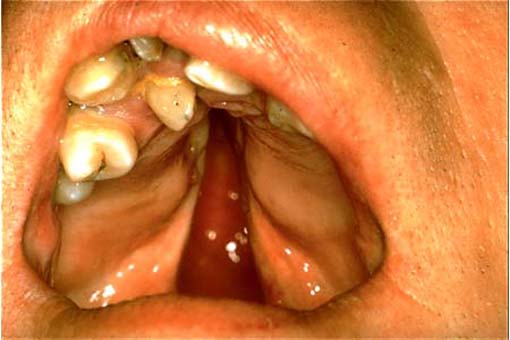

Gaumenspalte ........ Zum Kapitel